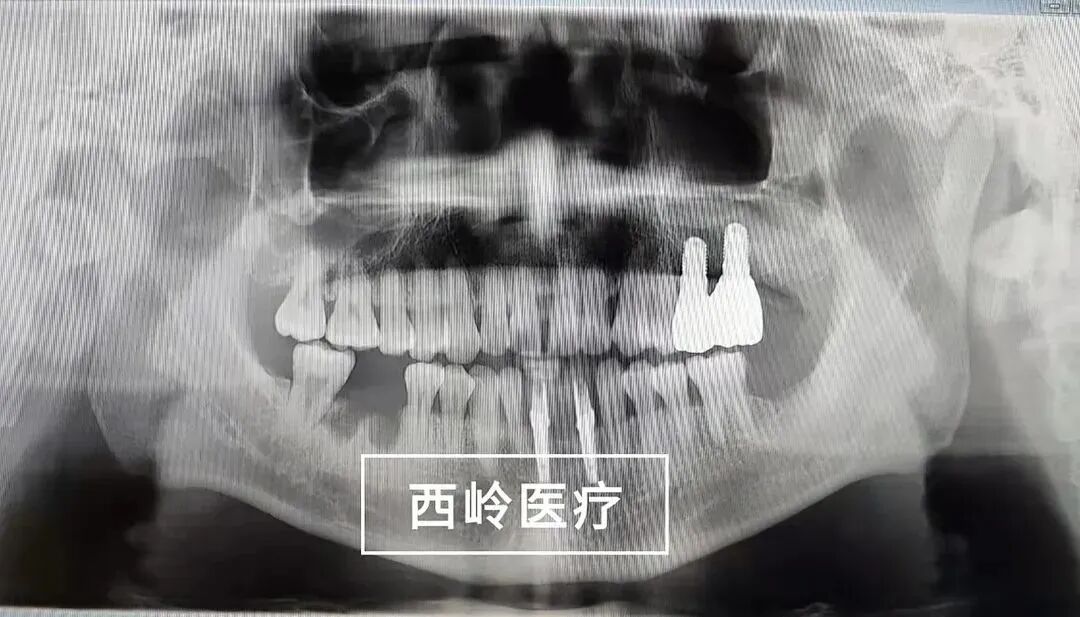

2021-11-30

戴牙后情況: